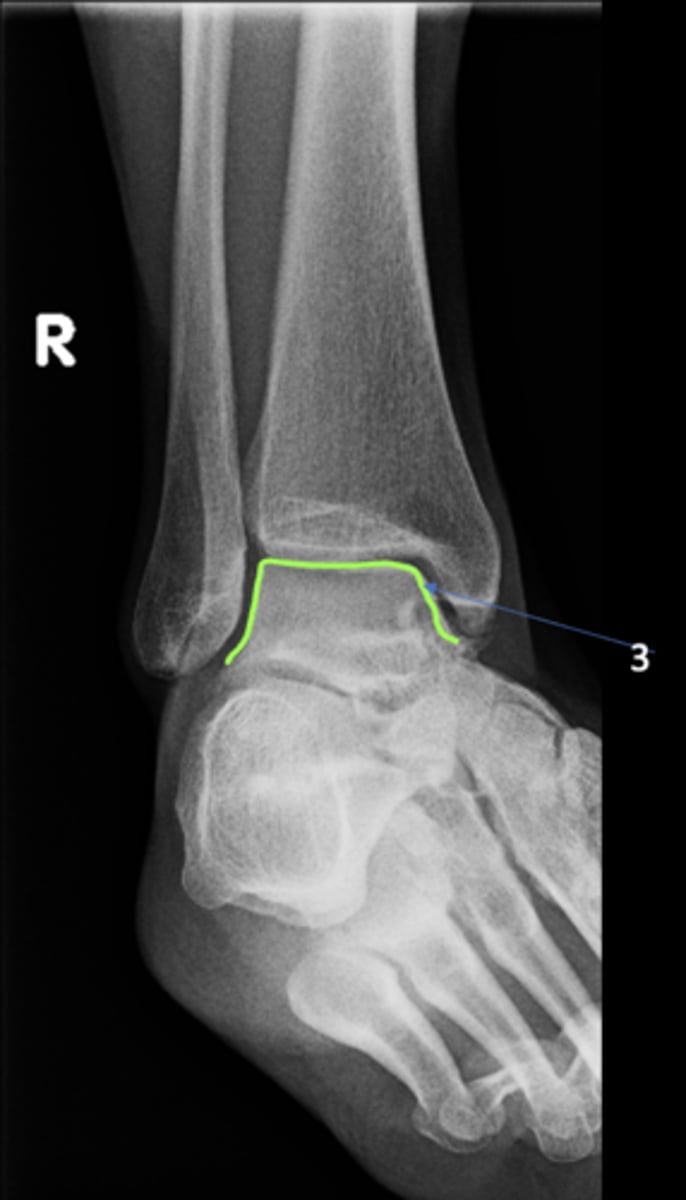

Right AP ankle

View?

<p>View?</p>

Tibial plafond

ID 12

<p>ID 12</p>

79

New cards

Trochlea of talus

ID 13

<p>ID 13</p>